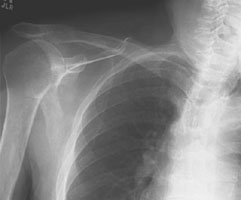

- Click on the image for a larger versionCAP chest radiograph. The usual appearance of an anterior shoulder dislocation on a frontal radiograph.